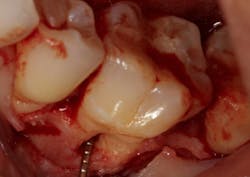

Another advancement in the field of periodontal regenerative medicine has been due to the use of growth factors, proteins, and stem cells. The ability to repair/regenerate a diseased tooth is often dependent upon the extent of the defect, namely the number of bone walls that are left surrounding the tooth. The more bone walls a tooth has left around it (maximum of four), the more blood supply, containment, and space maintenance your graft material will have (figure 5). Bone defects that have three to four walls missing are the hardest to repair and may be slated for extraction (figure 6). By adding growth-stimulating factors to your regular bone grafts (figure 7), an increase in osteopromotive potential occurs that can have the ability to overcome a deficiency of bone walls. (15) Simply stated, your bone graft can become alive, and teeth that were once unable to be repaired now have a chance.

Figure 6: Molar tooth with three walls missing around the palatal root. This tooth would normally be extracted.